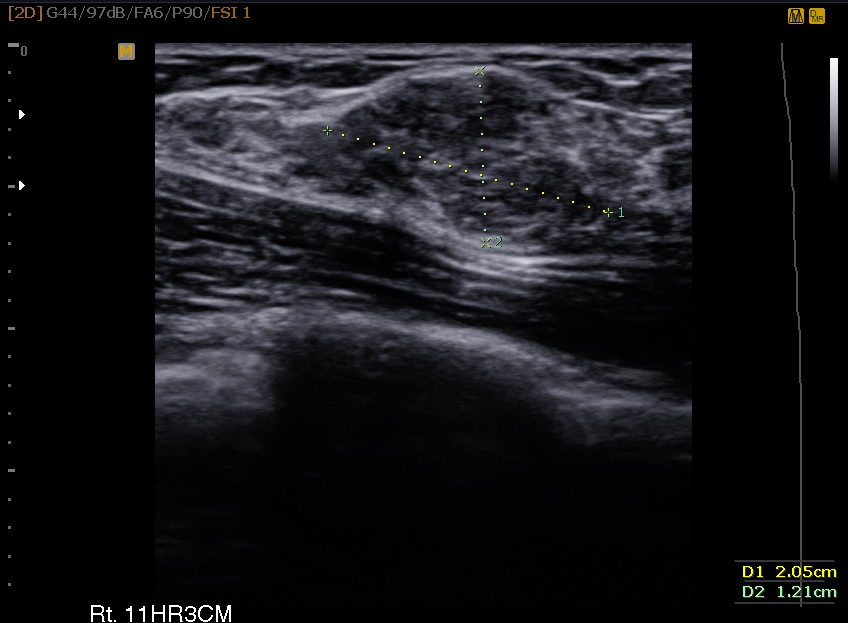

¸¾¸ðÅè½Ã¼ú»ç·Ê 25¼¼ ¿©¼ºÀ¸·Î ¿ìÃø¿¡ ¸¸Á®Áö´Â ¸Û¿ïÀÌ ÀÖ¾î ³»¿øÇÏ¿© Á¶Á÷°Ë»ç ½ÃÇàÇÏ¿´°í Á¶Á÷°Ë»ç °á°ú fibroadenoma Áø´ÜµÇ¾ú½À´Ï´Ù. ȯÀÚ ¿øÇϽÿ© ¸¾¸ðÅè ¼ö¼ú ½ÃÇàÇÏ¿´½À´Ï´Ù.